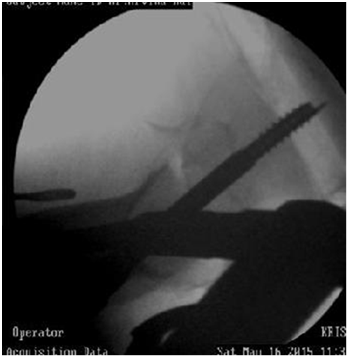

3. If reduction is not there the head screws will go into malposition (Figure 7).

Figure 7 Failure of closed reduction.